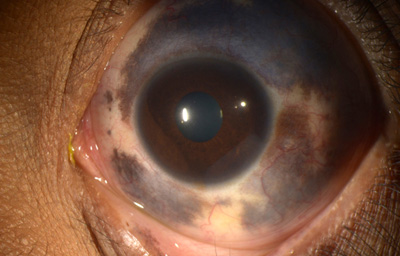

Sindrome de Axenfeld - Rieger, (ARS) Ambos ojos de un paciente

Archivo fotográfico Dr. Carmen Barraquer

Sindrome de Axenfeld - Rieger, (ARS) Ambos ojos de un paciente

Archivo fotográfico Dr. Carmen Barraquer